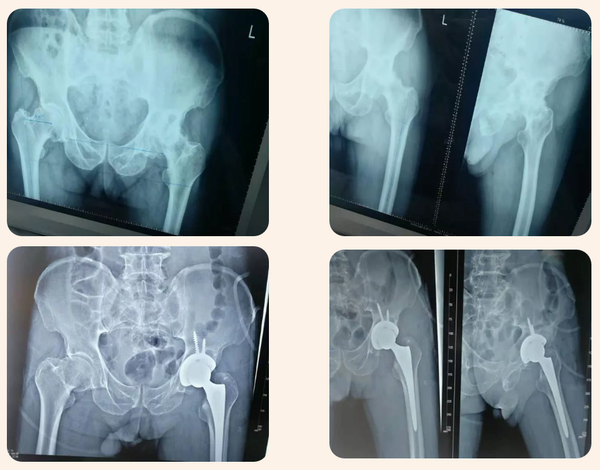

患者彭某某,男,77歲,因“左側髖關節疼痛5年余”來診入院。患者5年前在家無明顯誘因開始出現髖關節處疼痛,以左側疼痛較重,伴左膝關節疼痛,無發熱、無紅腫,無胸悶、呼吸困難、心悸、畏寒、發熱等癥狀,發病后曾到醫院就診,建議進行手術治療,患者不接受手術治療。近日患者左側髖、膝關節疼痛癥狀加重,到我院就診,門診以“左側股骨頭壞死”收住入院,入院后經積極完善相關檢查后診確為:1、左側股骨頭無菌性壞死;2、2型糖尿病。建議患者行左髖關節置換手術。

經積極做好術前準備后于11月1日在全麻下行左側全髖置換手術,手術順利,術后安全返回病房,術后第二天下地行走,術后給積極鎮痛、預防深靜脈血栓、術后康復等治療,術后順利康復出院。

股骨頭壞死(ONFH)又稱股骨頭缺血性壞死,是骨科領域常見的難治性疾病。股骨頭壞死是股骨頭血供中斷或受損,引起骨細胞及骨髓成分死亡及隨后的修復,繼而導致股骨頭結構改變,股骨頭塌陷,關節功能障礙的疾病。